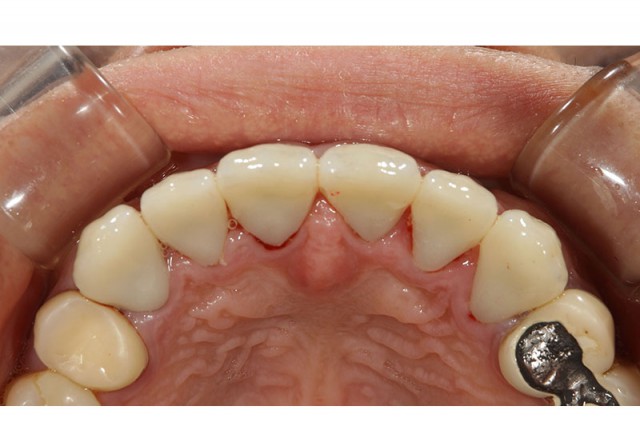

施術後

前歯6本を変更することで大変きれいな印象へと変わりました。オールセラミックは審美性に優れており、透明感やツヤがあり自然な色調で回復することができます。今回のような前歯には非常に相性が良い素材です。